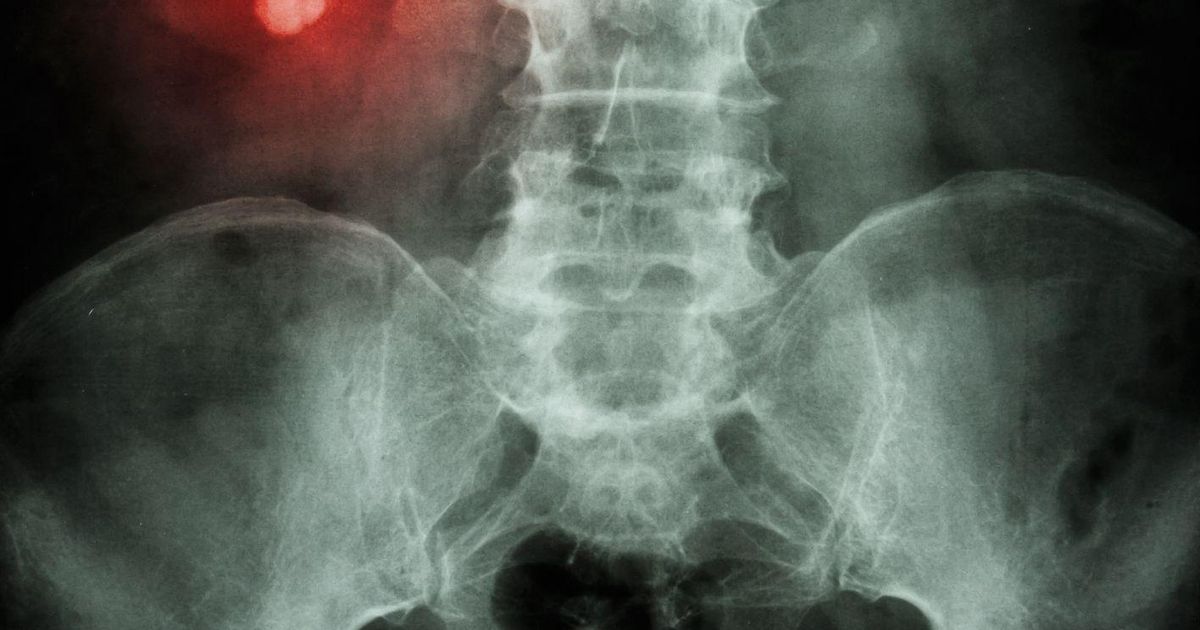

Uma em cada 10 pessoas sofre de cálculos renais, que podem bloquear o fluxo de urina através dos ureteres Crédito: Getty Images

As pedras nos rins atingem cerca de uma em cada dez pessoas. Elas se desenvolvem principalmente a partir de cálcio e oxalato que vazam do sangue para a urina. (Os oxalatos são compostos naturais encontrados em plantas e humanos.)

Em quantidades maiores, o oxalato e o cálcio podem cristalizar e acumular-se formando uma pedra. Os cálculos renais podem variar consideravelmente em tamanho, desde menos de um milímetro de largura até alguns centímetros.

Essas pedras causam problemas quando bloqueiam os ureteres, os dois tubos que transportam a urina dos rins para a bexiga. Se isso acontecer, pode causar fortes dores na região lombar, além de impedir o fluxo normal da urina. Isso pode causar infecção ou acúmulo de urina dentro e ao redor do rim.